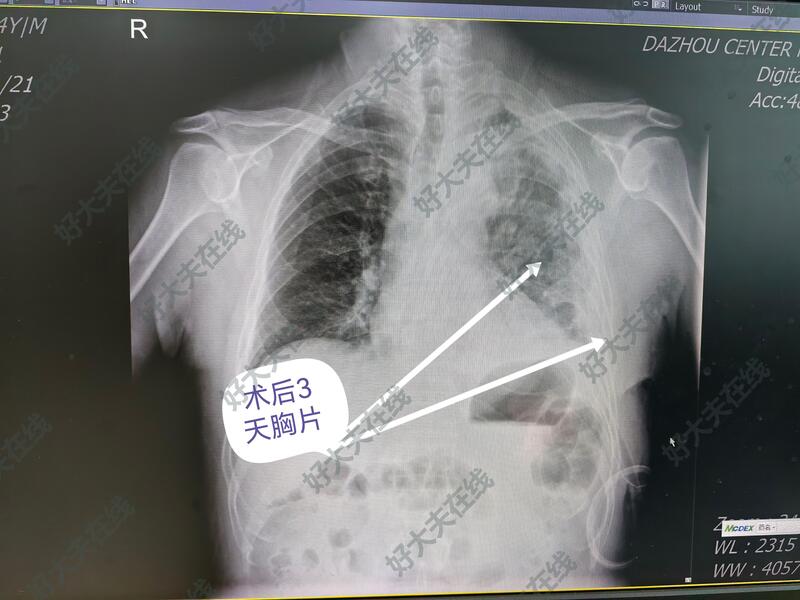

所传照片系第二例病人拔管时的胸片。